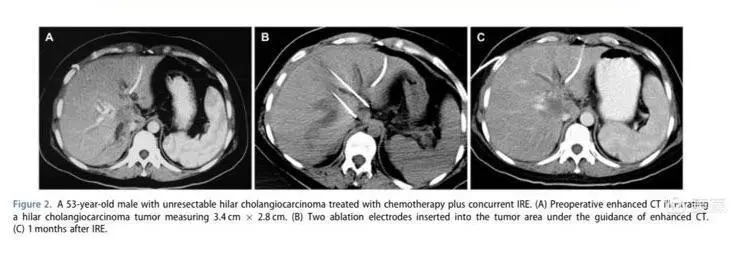

这是一个肝门部胆管癌纳米刀消融同步化疗的病例,双针平行分布,治疗后肿瘤完全没有活性。纳米刀在不可切除肝门部胆管癌的应用大有未来。